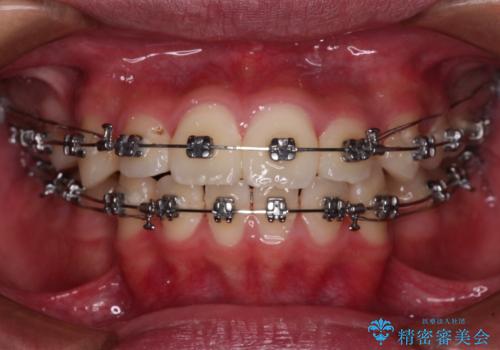

- 矯正装置

- メタルブラケット

- 前歯のデコボコと口元の突出感を気にして来院された患者様です。

上下前歯がくちばしのように突出していたため、上下左右の第一小臼歯4本を抜歯し、ワイヤー装置にて矯正治療を行うこととしました。